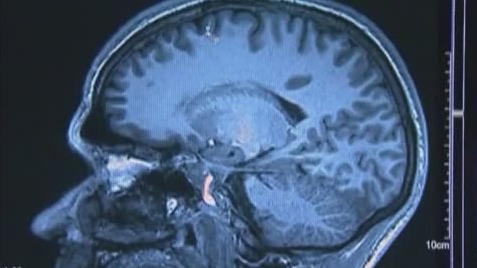

OAK HILL, Fla. - Meningitis is a highly contagious bacteria or viral infection that can spread through the exchange of respiratory and throat secretion, like spit, living in close quarters or by kissing.

The illnesses are often severe and include infections of the lining of the brain and spinal cord (meningitis) and bloodstream infections (bacteremia or septicemia), according to the Florida Department of Health.

Symptoms can include fever, headache, stiff neck, nausea, vomiting, light sensitivity, confusion and rash.